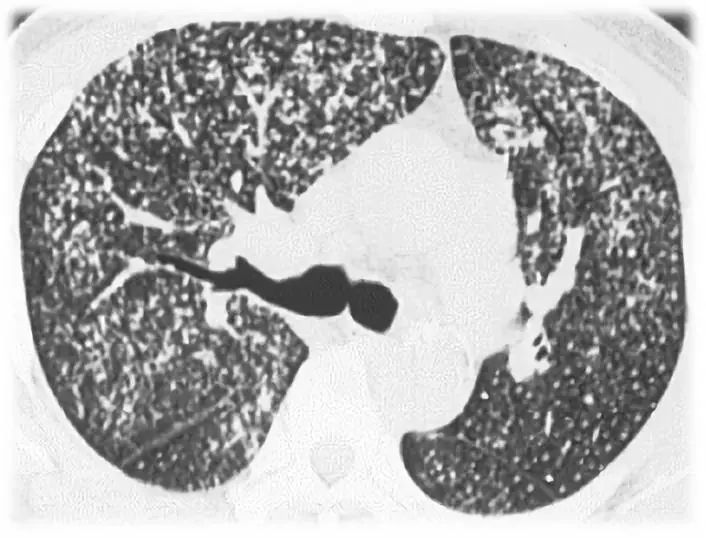

图 1-1结核的急性,亚急性或慢性血行播散:结节较多,多数较小,边缘清晰